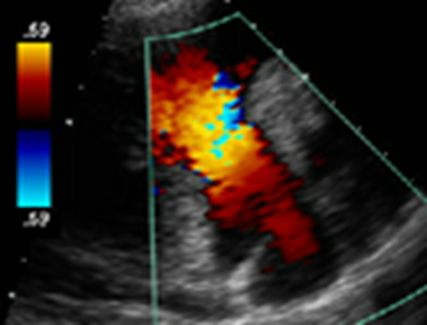

Tricuspid Regurgitation Color Jet

Assess TR jet width and length in all views. Adjust color gain, scale, and color box

Views in RVIT, SAX AO, A4C